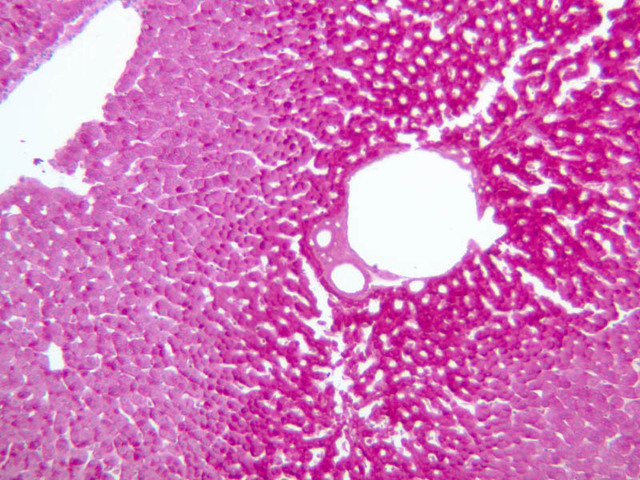

Scan slide B-36 (H&E [10x, 20x] [10x, 20x). Note that in this H&E preparation most of the pancreas consists of rather compactly arranged, darkly stained cells. The compact, darkly stained regions constitute the exocrine portion of the pancreas. (Of what organ does the exocrine pancreas remind you?) The endocrine portions of the pancreas consist of small bits, or islands, of more lightly stained tissue that is somewhat irregularly dispersed within the substance of the exocrine pancreas. Drawing on the name of their discoverer, the endocrine portions of the pancreas are known as the islets of Langerhans.

Using the high dry objective (B-36, H&E [40x, 40x-labeled]), study the structure of several acini. Note that the acinar cells are pyramidal in shape; note also that the acinar cells are clearly polarized: their basal cytoplasm (periphery of acinus) is quite basophilic, owing to large accumulations of RER, whereas their apical cytoplasm contains many acidophilic granules (zymogen granules) (B-36, H&E [10x, 20x, 40x-labeled]).

Now turn your attention to the system of pancreatic ducts. As you look for duct elements, bear in mind that the nuclei of duct cells tend to stain more lightly and to have less prominent nucleoli than do those of acinar cells. Begin by studying a number of different acini until you have identified several examples of centroacinar cells, which represent the initial segment of the duct system. Centroacinar cells are usually evident as lightly stained nuclei that lie, individually or in clusters of two or three, near the center of an acinus. Now look along the boundaries between acini for intercalated ducts (B-36, H&E [10x, 20x, 40x-labeled] [10x, 20x, 40x]), which appear in longitudinal section as trains of elongate, lightly stained nuclei and in transverse section as closely spaced, lightly stained nuclei surrounding a small lumen. Intercalated ducts drain into intralobular ducts, which are distinguished by their larger diameter. It is best to use the 10X objective as you begin your search for intralobular ducts (B-36, H&E [10x, 20x, 40x-labeled] [10x, 20x, 40x]). You want to be on the lookout for arrays of closely spaced nuclei surrounding a lumen. Conclude your study of the duct system by examining the connective tissue between pancreatic lobules for interlobular ducts, which may vary in caliber and epithelial lining (B-36, H&E [10x-labeled, 20x, 40x]).